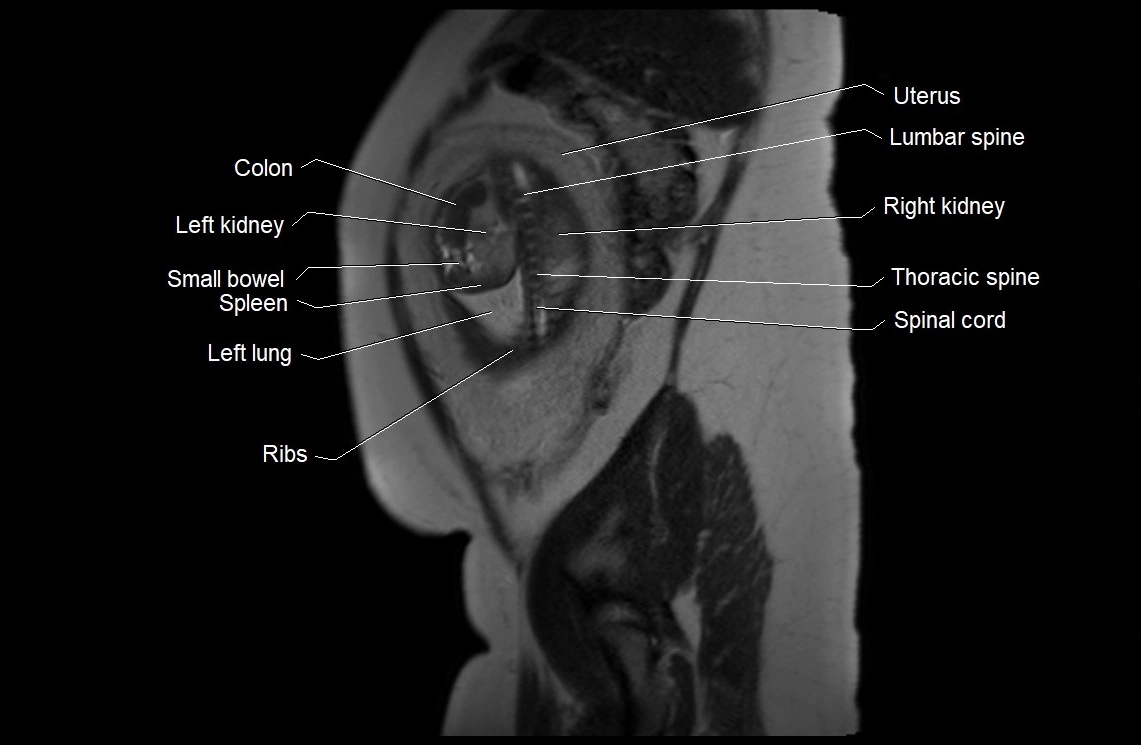

MRI Appearance

T2 HASTE (T2 GRE):

• Amniotic fluid shows very bright hyperintense signal

• Provides natural contrast against fetus and placenta

• Small particles (vernix) may appear as scattered hypointense foci within bright fluid